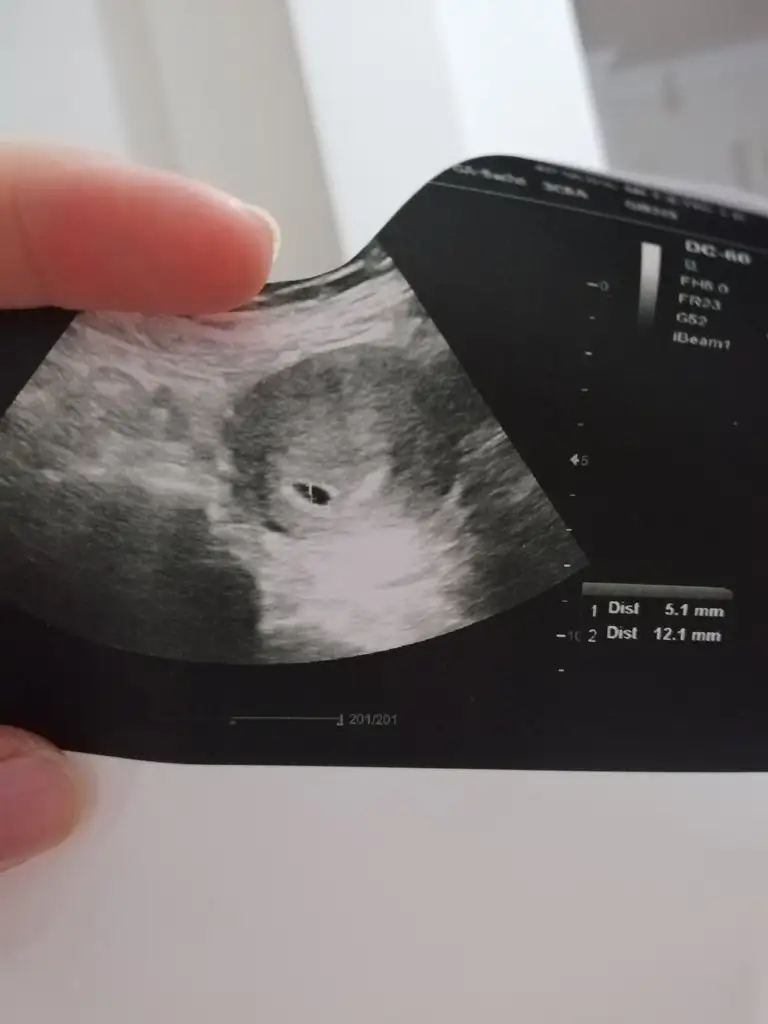

Canim peki ultrasondan sonra foto vermedi mi ? Ordan anlarsin kime gore solda ?Merhabalar doktor bana kese solda oluşmuş dedi. bana göre mi sol karşıdan bakınca mı sol aklıma gelmedi soramadım. böyle bidurumla karşılaşan var mı acaba

Hem de nasıl anlatılmaz yaşanır gerçekten o an ... hem korku hem heyecan karışık oluyor . Yolk görünüyor bakınca ortada yuvarlak olan . Vajinal baksaydı kesin görürdün bebisi . Neyse haftaya biraz daha heyecanCok sagol canimm insallah gorurumcok heyecanlaniyorum her doktora gidisimde

benim gittigim hicbir doktor ölçmüyor. Catlayacagim meraktan. Sadece kabataslak 6 hafta fka dedi o kadarAynen canim ama kesem cok tatli olmus teyzesi bakEki Görüntüle 2292051

Merhaba bana da yolk var dediler ama siz görebiliyorsunuz.? Bir de benim kesem aşagıda mı acaba doktora sormayı unutmuşum cuma soracam.. acaba aşağıda da ondan mı bu lekelenmelerim?Tebrikler canım yolk varsa bebek var demektir haftaya görürsün annesi

yolk sac cok net belli oluyor. Bence asagida olsa doktor mutlaka soylerdi uyarirdi seni. Lekelenme icin ilac kullaniyomusunMerhaba bana da yolk var dediler ama siz görebiliyorsunuz.? Bir de benim kesem aşagıda mı acaba doktora sormayı unutmuşum cuma soracam.. acaba aşağıda da ondan mı bu lekelenmelerim?